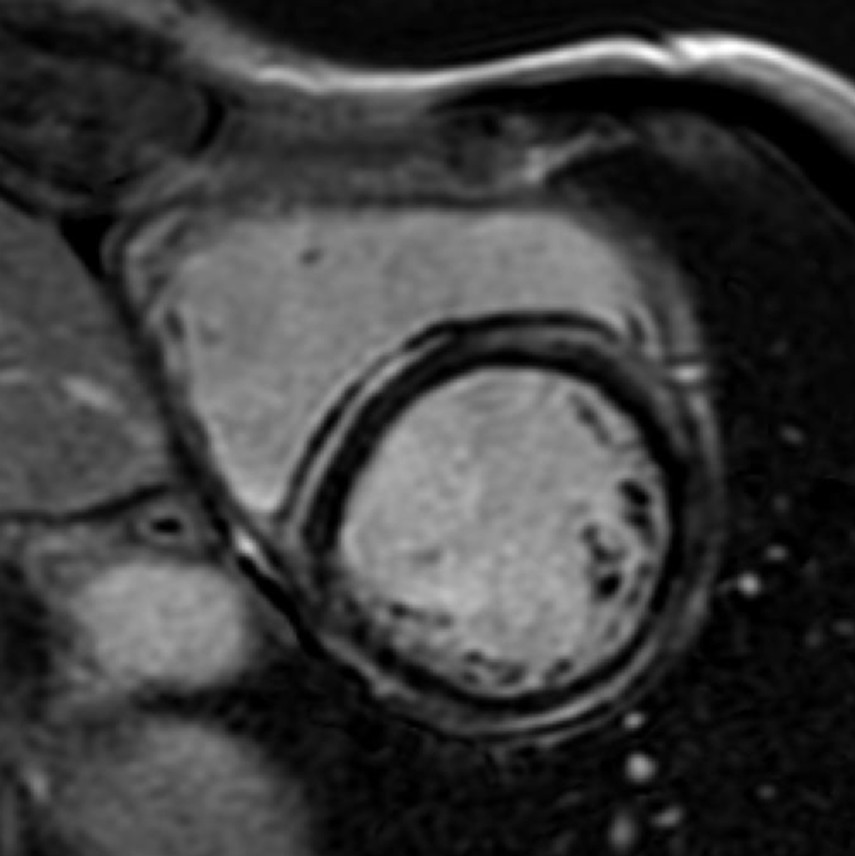

Fifty shades of grey

Caso condiviso da Marcello De Santis